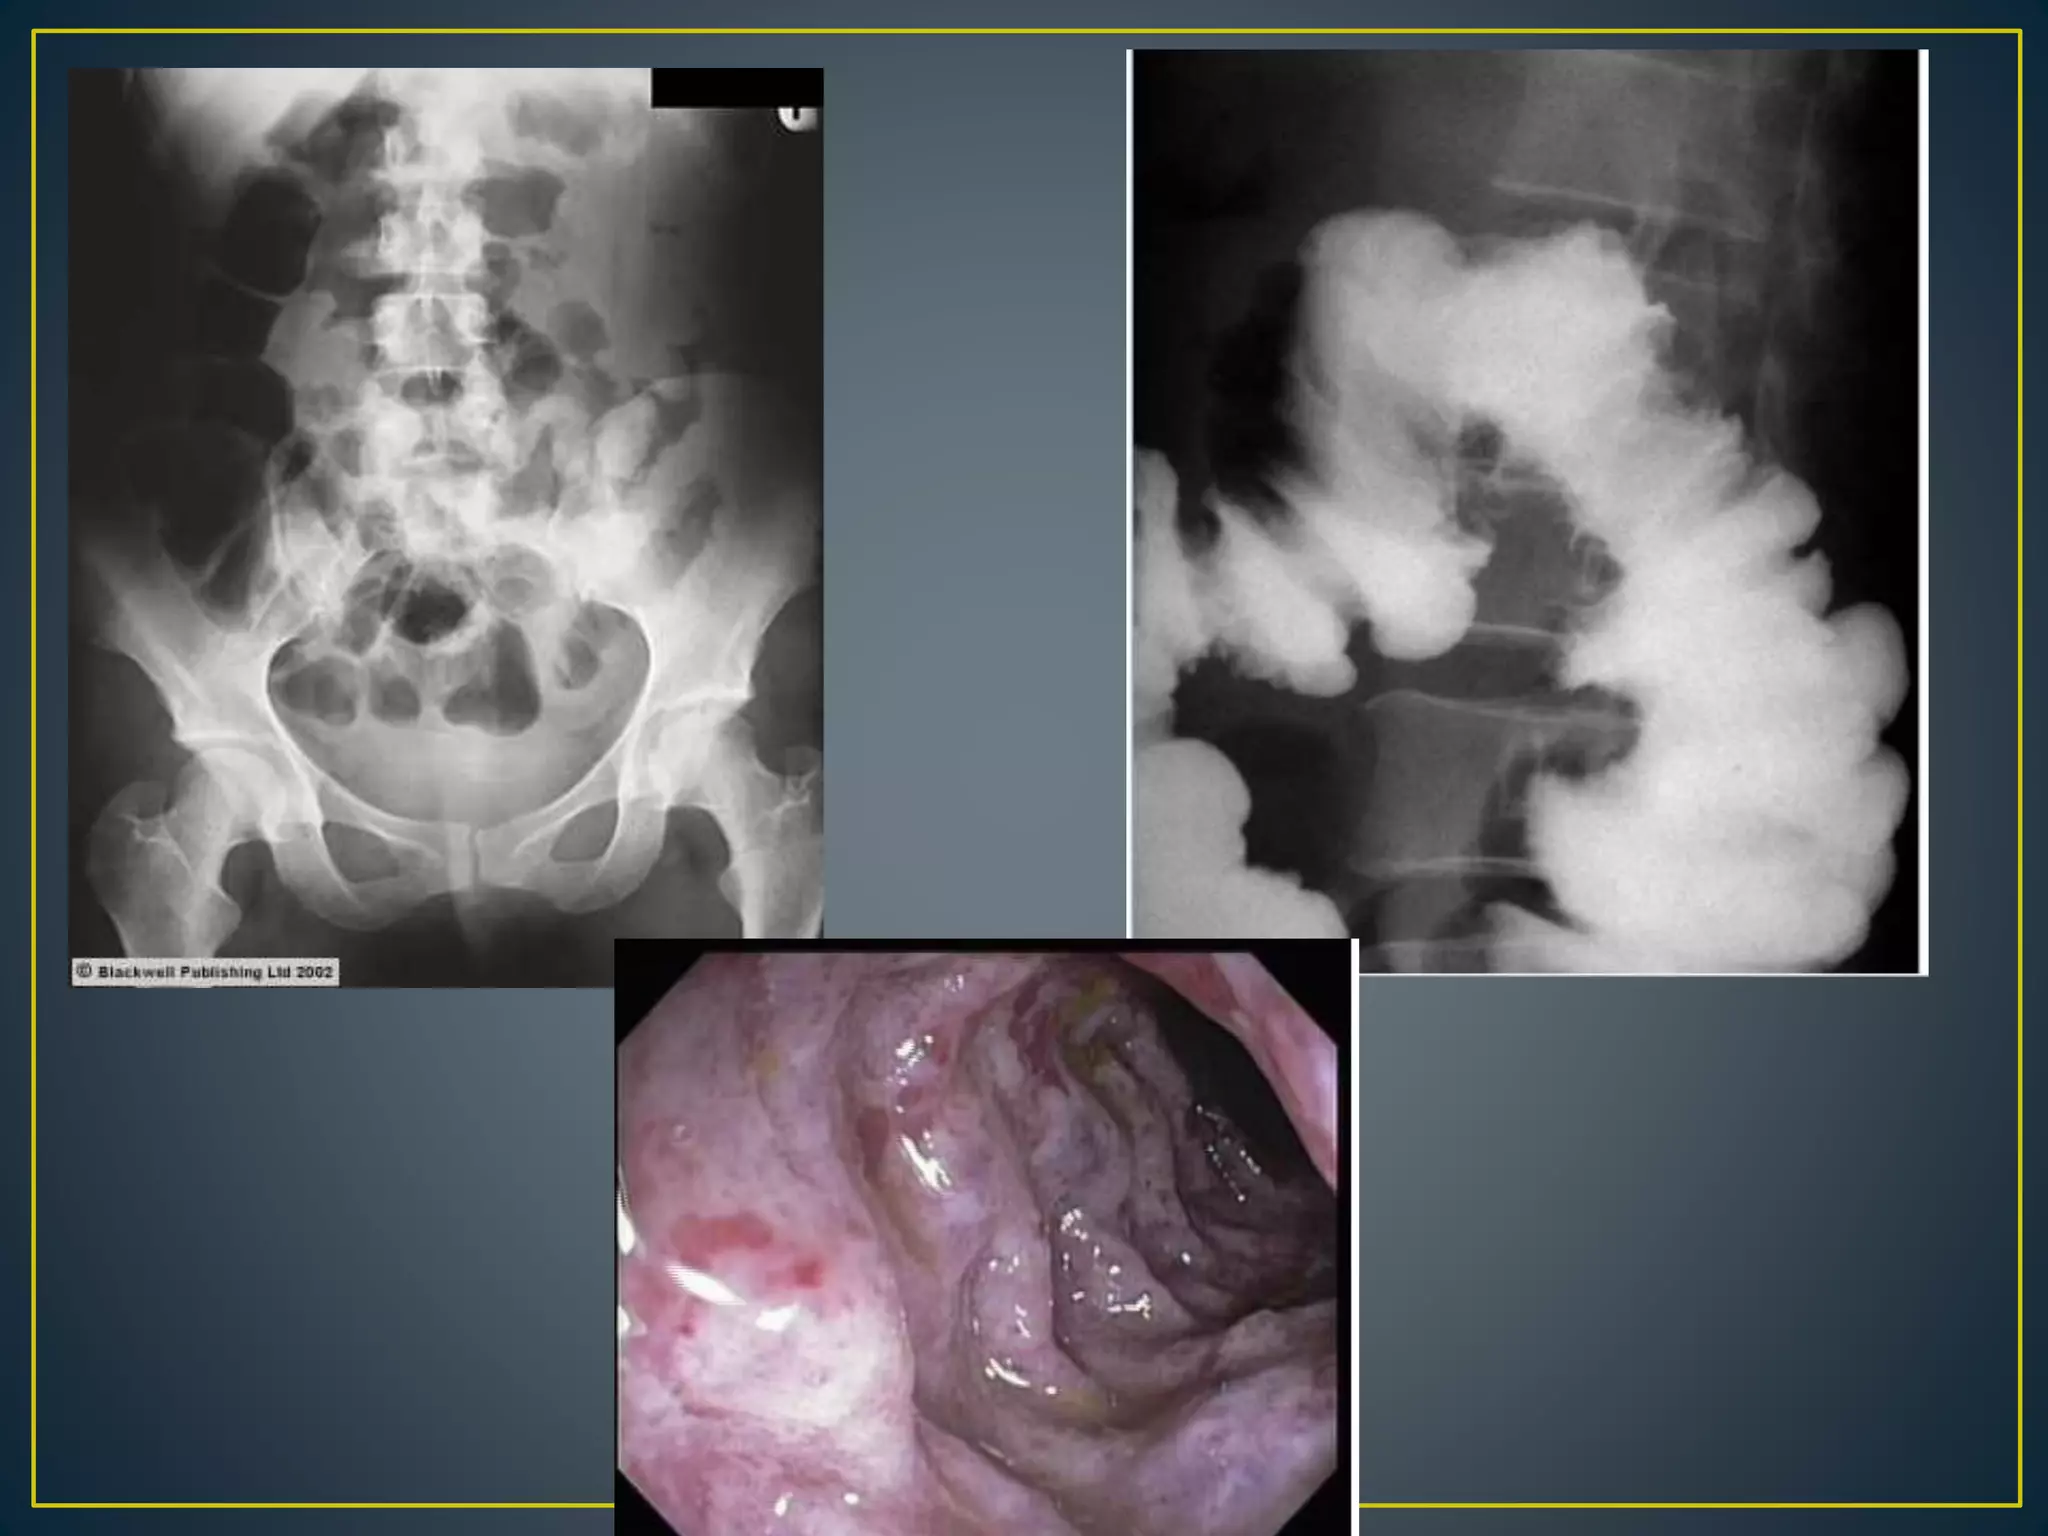

• Diverticulosis Has been implicated as the source of

bleeding in as many as 60% of cases of lower GI

bleeding.

• The diverticula are more prevalent in the left or sigmoid

colon, but positive arteriography findings for bleeding

localizes the bleeding to the right colon in 60% of cases

• Diverticular bleeding does not have a characteristic

appearance unless contrast fills the diverticulum itself

—MDCT scan obtained in 71-year-old woman with hematochezia from bleeding sigmoid

diverticulum shows extravasated contrast material (arrow) flowing into lumen.

Tew K et al. AJR 2004;182:427-430